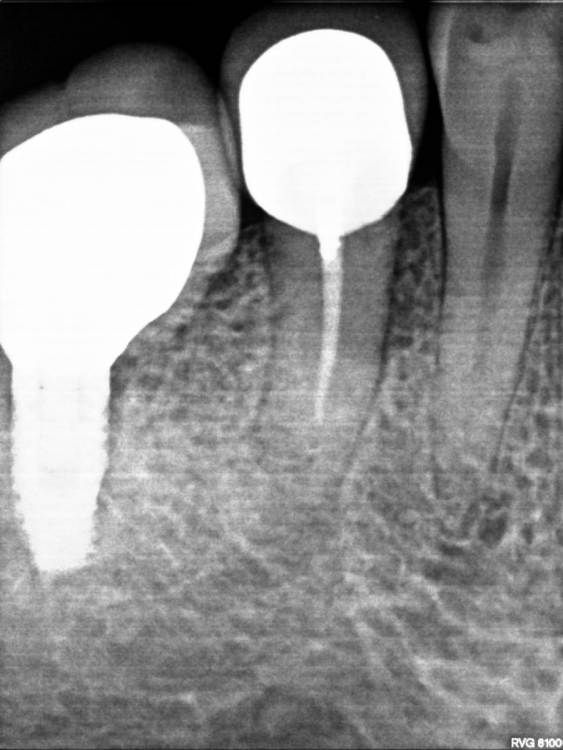

Анатолий2022 Опубликовано 7 апреля, 2022 Поделиться Опубликовано 7 апреля, 2022 Здравствуйте. Опухла десна под зубом, сделал снимок посоветуйте, что делать к какому специалисту обращаться. Заранее благодарю Ссылка на комментарий

Анатолий2022 Опубликовано 7 апреля, 2022 Автор Поделиться Опубликовано 7 апреля, 2022 В дополнение к вышеизложенному. Терапевт осмотрел, постучал по зубам сказал ничего нет, почистил карманы ультразвуком. а имплантолог диагностировал периодонтит. Вопрос: кому верить Ссылка на комментарий